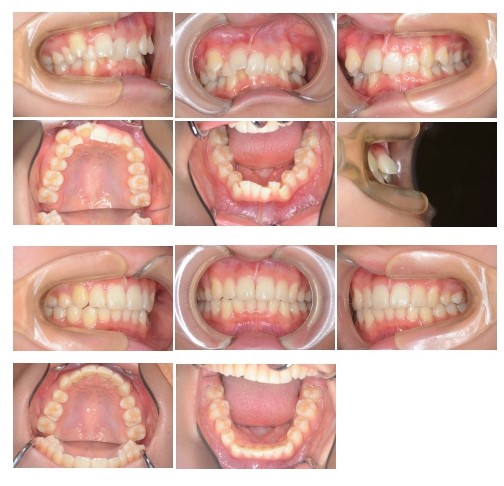

主訴:歯のガタガタ

診断名:過蓋咬合 上下顎叢生

年齢:15歳

装置名:マルチブラケット装置

治療費(施術料 装置料 調整料): 68万(税込み)

インプラントアンカー2本・薬:41600円(税込み)

治療期間:2年2か月

考えられるリスク:矯正歯科治療に伴う一般的なリスク

(歯根吸収、虫歯、歯周病、歯の移動時の痛みなど)